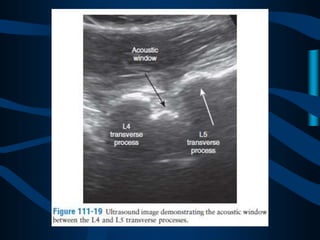

PARAESPINOSO

MEDIAL